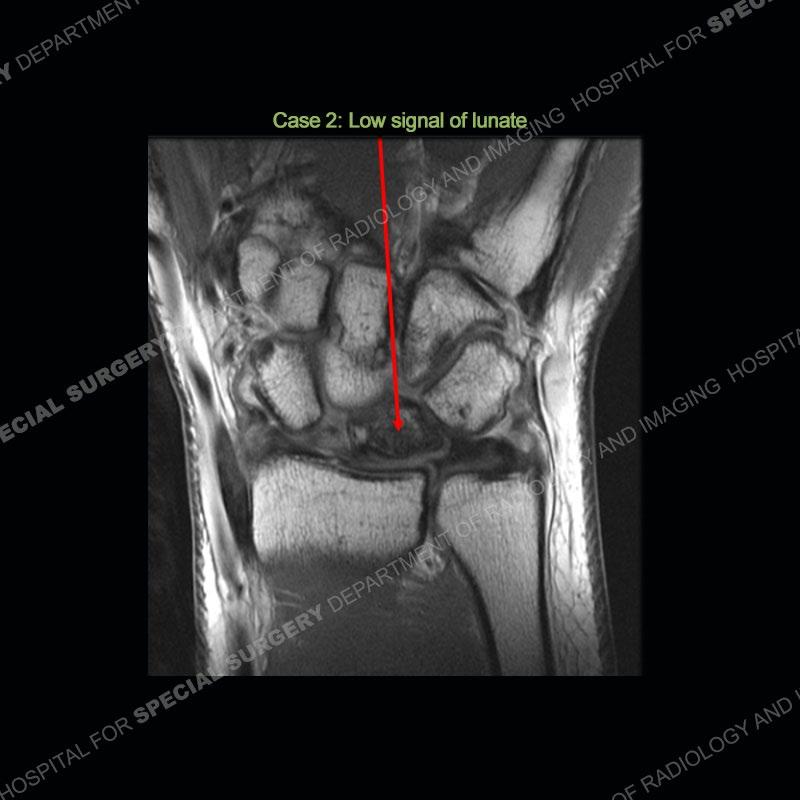

Both cases demonstrate similar findings to slightly less and more conspicuous degrees. The radiographs show sclerosis and fragmentation/collapse of the lunate. The CT images for case one just further clarify the architecture of the lunate. The MRI images show a slightly greater degree of variability but with overall persistent areas of low signal of the lunate on all pulse sequences and with a loss of the geometry of the lunate indicating collapse and fragmentation.

A well recognized but still poorly understood entity with necrosis and collapse representing the end stage of the pathology. The reasons for the necrosis are likely multifactorial and relate to the anatomy of the wrist inclusive of ulnar variance and the anatomy of the vasculature to the lunate. Other inflammatory, biological processes and overuse/trauma also likely play a role in the development of the necrosis. The disease manifests by sclerosis of the lunate followed by collapse and fragmentation. This is then followed by abnormal orientation of the scaphoid in a palmar flexed position and then adjacent arthritis. These latter processes were not the focus of this case presentation. The MRI will show areas of low signal on all pulse sequences indicating the areas of devitalized bone. The foci of slightly increased signal are in keeping with areas of maintained perfusion and highlight the variable architecture and findings of Kienbock’s. The fragmentation and collapse of the bone are seen well on both CT and MRI.